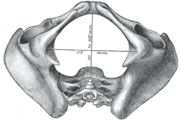

Diameters of pelvic inlet